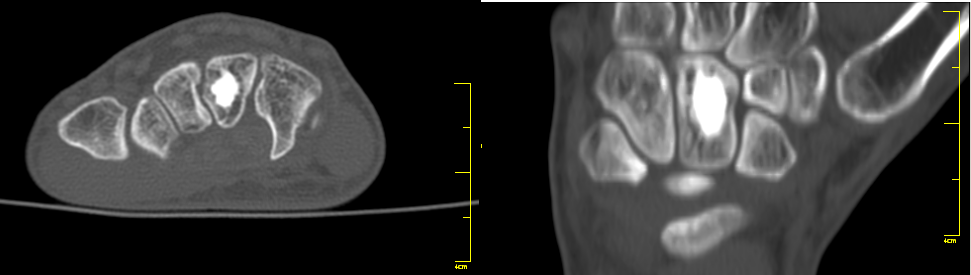

Hallazgo radiológico característico

- ✅ Imagen: Masa ósea densa, homogénea, bien delimitada, de contornos nítidos, adherida a la superficie cortical (clásico/parosteal) o intramedular (isla ósea). Tamaño típico <3 cm. La TC es la mejor prueba para valorar su extensión y relación con estructuras vecinas.

5) Imagen

4.1 Radiografía simple

- 🩻 Masa ósea lobulada, adherida a la superficie cortical (en osteomas clásico y parosteal) o intramedular (en islas óseas).

- 🩻 Aspecto radiográfico de hueso maduro, con una densidad que puede variar desde hueso esponjoso (trabecular) a hueso compacto denso (haversiano).

- 🩻 Densidad uniforme y contornos nítidos.

- 🩻 Tamaño generalmente menor de 3 cm de diámetro (pueden ser más grandes).

- 🩻 La lesión es circunscrita, de extraordinaria densidad, redondeada.

4.2 Tomografía computarizada (TC)

- 🩻 Es la técnica de elección para:

- 🔹 Delimitar con precisión los márgenes del tumor.

- 🔹 Evaluar la extensión hacia estructuras vecinas (órbita, fosa nasal, canal medular).

- 🔹 Planificar la cirugía.